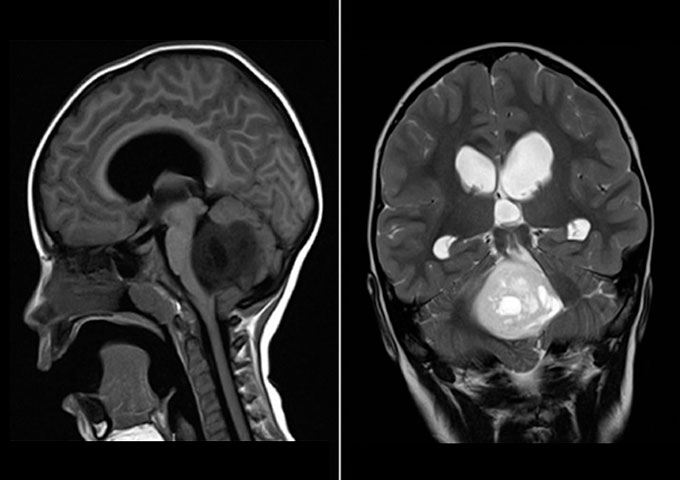

El tumor de la fosa posterior es una neoplasia que ocupa la fosa craneal posterior que se encuentra limitada por el clivus, en la zona inferior por el foramen mágnum, posterior por la concha del hueso occipital y a sus laterales por la porción petrosa mastoidea del hueso temporal y arte del hueso parietal (Fajardo,2001). Este tumor es el segundo tipo de cáncer infantil más común; representa en la población pediátrica el 48% del total de esta y su incidencia es de 4,5 por cada 100.000 niños. Afecta en mayor parte al género masculino con 57% del grupo poblacional reportado. Dosterceraspartes aproximadamente, de todos los tumores intracraneales que aparecen en niños entre 2 y 12 años de edad, son los infratentoriales pertenecientes a la zona posterior del cerebro (Cano, 2010).

| Tumores de fosa posterior en pacientes pediátricos y su correlación clínica, radiológica y anatomopatológica | 1. Quirúrgica 2. Medicamentos (anticonvulsivantes: difenil hidantohina dosis de 4-8 mg/kg/día) 3. Radioterapia 4. Terapia con Gamma Knife (Tipo de radiocirugía estereotáctica): Bisturí de rayos gamma 5. Agentes quimioterapéuticos (drogas: nitrosoureas, procarbazina, fluoracilo, metrotrexato y cisplatino). 6. Resección quirúrgica |

El mayor porcentaje de tumores de fosa posterior se registró en los grupos de edad de 1 a 5 años y 6 a 10, que representaron 45 y 28%, respectivamente. El mayor volumen estadístico de tumores de fosa posterior fue de astrocitoma (34%), seguido de meduloblastoma (21.3%), ependimoma (19.1%), glioma (12.8%), oligodendroglioma (4.3%), ganglioglioma, meningioma, hemangioblastoma, papiloma de plexo coroides (2.1%). Los síntomas iníciales que sintieron los pacientes con tumores de fosa posterior fueron: cefalea y vómito (40.4%) y solo vómito (25.5%). El 53.2% de los pacientes no tuvo síntomas acompañantes (Cano,2010). |